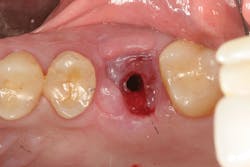

The most critical aspect of any implant system is the interface between the implant fixture and its surrounding bone (figures 1-5). Integration between the fixture and its surrounding bone is the foundation of modern implant dentistry. There is little we can do to modulate bone healing, but we can modify the implant fixture itself.

Figures 1-5: Figures 1 through 4 illustrate, respectively, a seven-year follow-up visit and a three-year follow-up visit of two different implant systems. Implant No. 22 (figure 5) shows peri-implant radiolucency following functional loading, indicating fibroencapsulation and loss of integration into bone, necessitating removal.